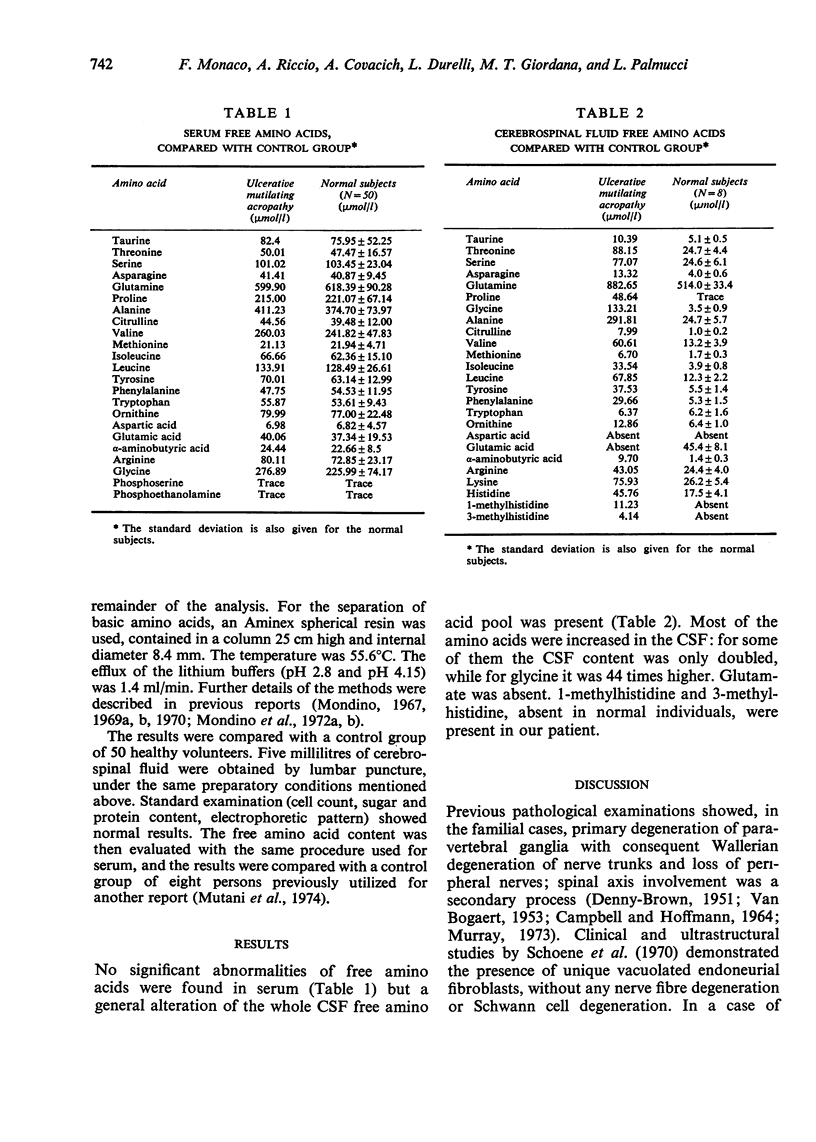

A case of sporadic ulcerative mutilating acropathy is described. Muscle biopsy showed signs of neurogenic atrophy. Motor nerve conduction velocity was slightly reduced. The muscles of the foot were completely unresponsive to electric stimulation of both femoral nerves. The content of free amino acids in serum and cerebrospinal fluid was determined by ion exchange chromatography, and compared with a control group. While in serum no significant changes were found, in CSF most amino acids showed great alterations, mainly consisting in an increase. It is suggested that the primary disturbance may be located in the spinal nerve roots.